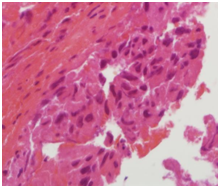

A specimen labeled as left frontoparietal hematoma - ? cavernoma from a 41 year old non-hypertensive female patient on ventilator was received for histopathologic examination. The patient was transferred from outside hospital to neurosurgical department of our hospital for craniotomy and evacuation of intracerebral hematoma. The clinoradiologic diagnosis was spontaneous intracerebral hematoma with intraventricular extension with normal ventricle, probably due to cavernoma. The microscopic examination of the specimen revealed extensive hemorrhage with peripherally placed mono-nucleated and multinucleated atypical cells. The mononucleotide cells were medium to large size with abundant cytoplasm and central large hyperchromatic nuclei. The multinucleated cells were large with abundant eosinophilic cytoplasm and hyperchromatic multinucleated bizarre nuclei. They were considered as cytotrophoblasts and syncytiotrophoblasts respectively (Figure 1-4). Immunohistochemistry showed that the atypical cells were CKAE1AE3 +, HCG+, GFAP-, CD31- and Vimentin- (Figure 5 to 10). A thin rim of GFAP positive glial tissue was seen in one fragment. Based on these findings, a diagnosis of metastatic choriocarcinoma was made. The patient survived the surgery and started recovering neurologically, but chose to go back to her own country for further management. So, we could not get any details of her obstetric history or previous medical illness.

Figure 3 Cytotrophoblasts.

Figure 1 Cytotrophoblasts.